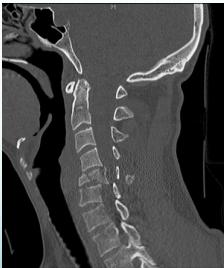

Advanced Imaging

- CT for difficult areas (upper/lower C, upper T)

- Shows structural damage of vertebrae and vertebral fragments into the canal

Fractures of C2 (Hangman’s Fracture)

- Hyperextension/distraction injury

- In MVA when forehead strikes dashboard

- Unstable

- May cause death (why?)

discontinuity of the central axial spinal pillar

Fractures of C2-Odontoid

- Identified easily by:

- Open mouth view

- CT scan